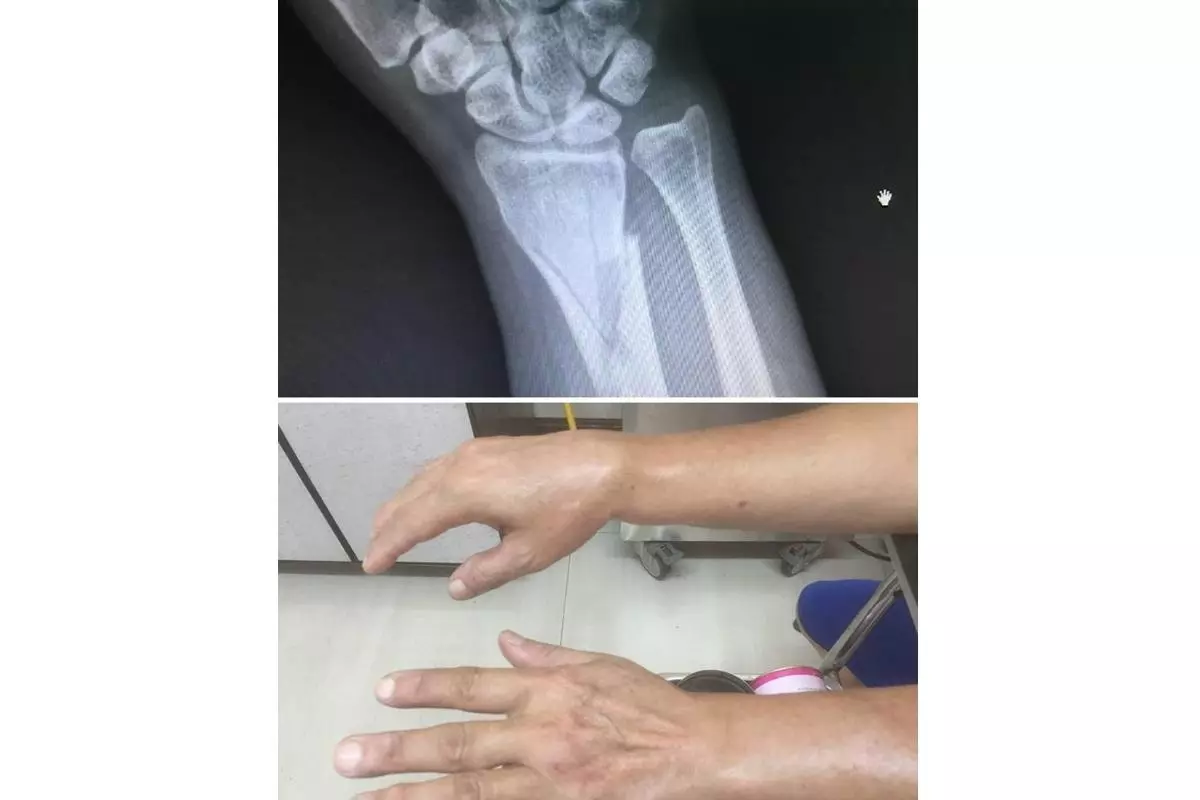

劍鳴損傷接骨院主要服務項目涵蓋骨折、骨頭移位、運動傷害、一般扭傷、身體酸痛、脫臼、五十肩、病理按摩、拉傷等各類筋骨問題。不論是上班族常見的肩頸僵硬、久坐引發的腰背痠痛,或是長輩行走不穩造成的跌倒受傷,以及運動族群常見的肌肉拉傷與關節不適,都能在此獲得專業協助。

劍鳴損傷接骨院能獲得廣大患者信賴,關鍵在於四大核心優勢。首先是專業合法的接骨技術,李院長持有國術損傷接骨證照,並具備醫院實務經驗,治療過程安全可靠。其次是精準診斷與對症處理,針對不同傷勢深入評估,避免制式化療程。第三是親切細心的服務態度,讓患者清楚了解自身狀況,建立治療信心。最後則是價格公道透明,多年來堅守誠信原則,讓民眾能以合理費用獲得高品質服務。